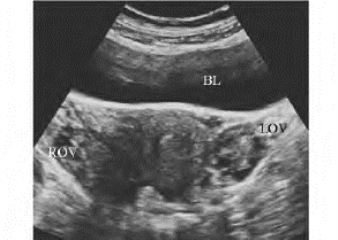

1.37.6六、卵巢非赘生性疾病

1.37.7七、卵巢囊性肿瘤

1.37.9九、超声诊断卵巢肿瘤的意义